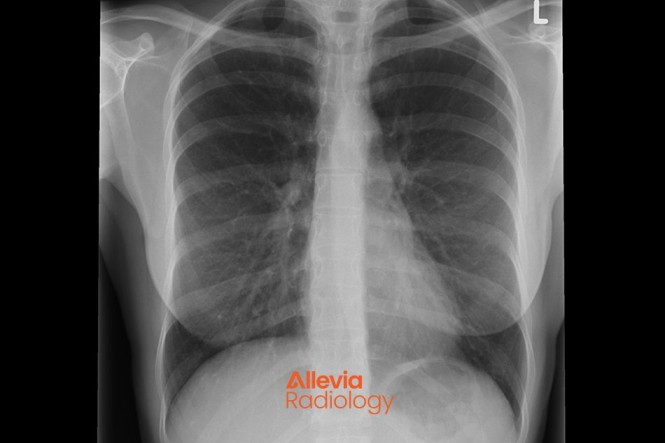

Healthify's radiology topics are brought to you in collaboration with Allevia Radiology (formerly Mercy Radiology).